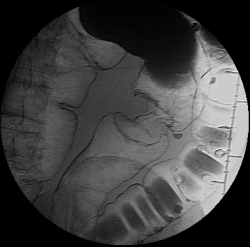

Пациент 76 лет, направлен на ирригоскопию в наше отделение с предворительным обоснованием: образовование восходящего отдела ободочной кишки. Зарание был обговорен хирургом, по поводу выяснения протяженности процесса. Была проведена колоноскопия: "Аппарат проведен до слепой кишки. Просвет толстой кишки нормальный. Стенки толстой кишки эластичные. Толстая кишка нормотоничная. Складки толстой кишки нормальные. Гаустры толстой кишки глубокие. В восходящей кишке виден инфильтрат с бугристой поверхностью, захватывающий все стенки кишки (циркулярно). На поверхности инфильтрата видны мелкие очаги некроза. Инфильтрат суживает просвет кишки. Протяженность инфильтрата до 10 см. ЗАКЛЮЧЕНИЕ: Инфильтративное деонтологическое заболевание_восходящей кишки"

Ну "перво - наперво" шикарно видно "сужение"

Это исследование я проводил сегодня утром, помимо данного участка с "органикой" есть ещё один участок, который отчётливо видно на МСКТ при анализе изображений, но почему то мой более старший коллега ни стал об этом указывать ссылаясь на то, что преригатива скопического и эндоскопического исследований, у нас там конечно ни шуточная баталия разгорелась, и вообще поставил данный участой симметричного сужения подвопросом:

Именно этим мне и показался данный случай интересным, получается именно данный участок видели эндоскописты, а это участок поперечного отдела ободочной кишки, даже почти селезёночный угол, чётко видно на МСКТ. И получается что первично-множественный рак толстого кишечника, если я не прав поправте меня.